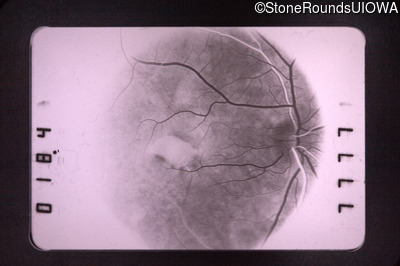

Visit at age: 59 years

Fluorescein Angiography - Left - 20/40

Exemplar